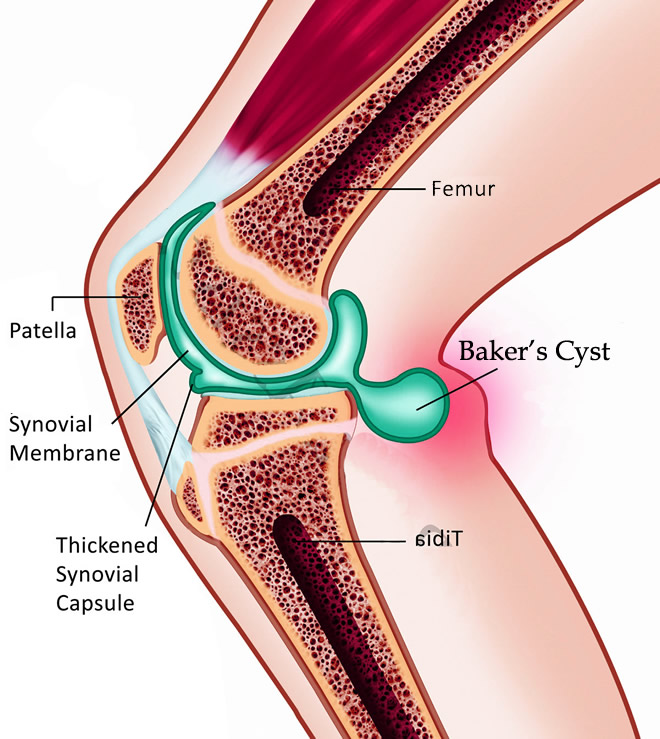

A Baker's cyst is a fluid-filled cyst that causes a bulge and a feeling of tightness behind your knee. The pain can get worse when you fully flex or extend your knee or when you're active.

A Baker's cyst is usually the result of a problem with your knee joint, such as arthritis or a cartilage tear. Both conditions can cause your knee to produce too much fluid, which can lead to a Baker's cyst.

It is very important to know that the Bakers Cyst is an effect of an underlying Condition. It is not the primary problem. So getting the cyst drained or removed without treating the underlying condition will just cause the Cyst to reappear.

Although a Baker's cyst may cause swelling and make you uncomfortable, treating the probable underlying problem usually provides relief.